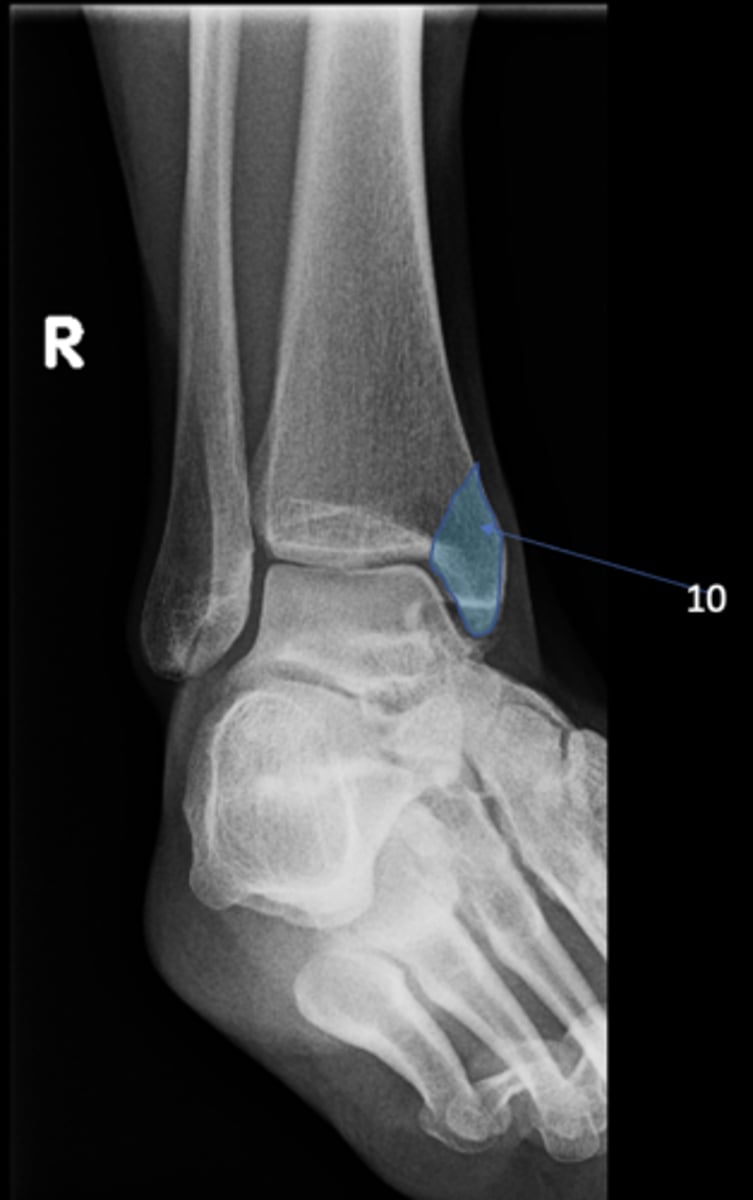

Right AP ankle

View?

Lateral malleolus

ID 11

Tibial plafond

ID 12

Trochlea of talus

ID 13

Distal tibiofibular joint

ID 14 (joint)

Tibiotalar joint

ID 17 (joint)